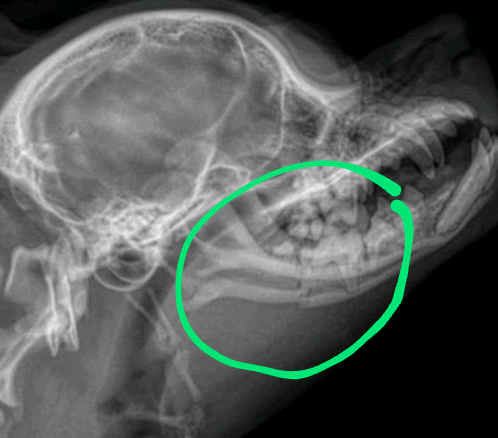

Oiê, bom eu criei essa vakinha para mel, uma cachorrinha de um “querido” inquilino que abandonou ela depois que ela de machucou. Ela caiu de uma altura de mais ou menos 3 metros e fraturou o queixo.

Eu e minha família custeamos a ida ao veterinário e aos remédios, ração especial e sachê por conta que a coitadinha não pode mastigar, porém não temos como arcar com a cirurgia dela no momento, pois é uma cirurgia que necessita urgência.

Ela precisa colocar uma placa de titânio e requer anestesia especial por ser um cachorro braquicefálico. Peço que do fundo do coração que se você puder contribuir com qualquer valor e divulgação, por favor contribua. Um ser vivo como eu e você 🫵🏼 tbm merece dignidade e tratamento adequado.